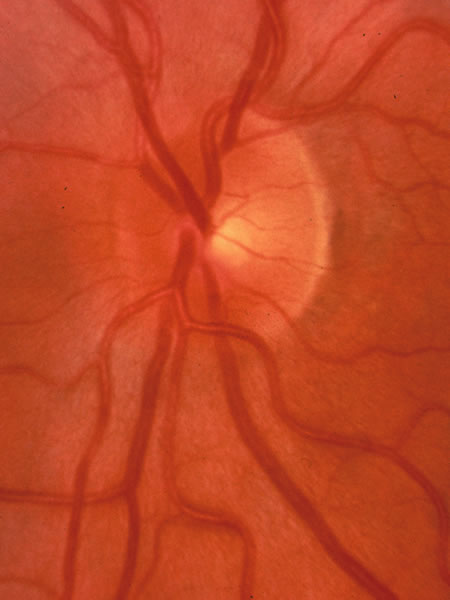

Fig. 9. Normal small disc with no cup because it is filled with neuroretinal tissue, which consists of the axons leaving the eye to form the optic nerve, along with the astroglia and the capillary bed.